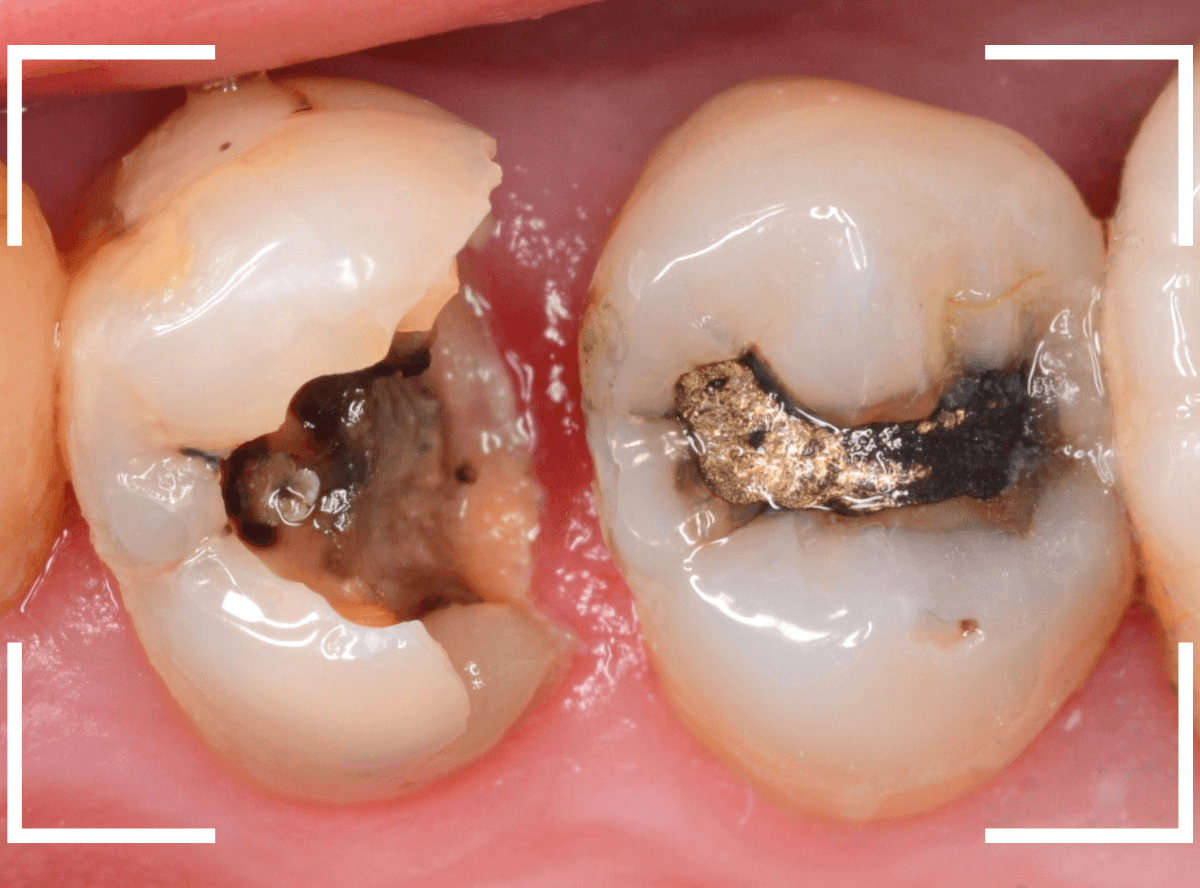

Case.7 劣化した金属の下がひどい虫歯

今回は、歯が欠けたという事で来院された患者さんです。

つめものの中で虫歯が大きく進行してしまい、何かの拍子に歯が欠けてしまった状態です(左側)。

右隣の歯もつめものが劣化して中に虫歯が進行しているのが見えます。

早速、虫歯の治療を開始すると、想定通り虫歯で歯の中はボロボロになっています。

虫歯を取りきったところで、歯の神経が部分的に露出し、出血が見られました(露髄)。

かなり厳しい状況で、どうするか悩むところでしたが・・・。

幸い、神経からの出血も少なく、神経が露出している範囲も小さかったため、神経を残せる可能性に賭けて、神経を保存する処置をしました。

隣の歯の虫歯の処置をしながらの経過観察になります。

痛みが出ませんように。。。